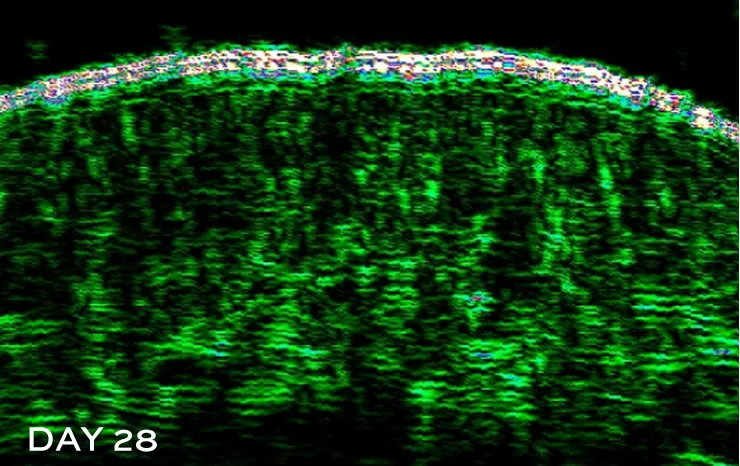

Test performed on 30 women aged 40–60, in perimenopause or menopause, applying Essential Shock (R)Evolution Pro-Exo Collagen Matrix twice daily for 28 days.

Skin image with ultrasounds

The color green indicates stronger, denser-looking areas of the skin, with:

Enhanced DENSITY

The upper white line indicates epidermis thickness.